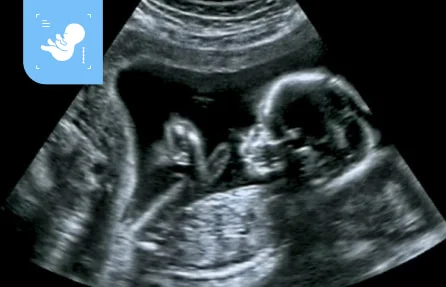

Veja seu bebê em tempo real com tecnologia

5D 8K

Com cuidados de qualidade e confiança, utilizamos tecnologia de ponta para realizar exames de ultrassom e ultrassom 5D 8K. Assim, as futuras mães podem visualizar seus bebês em tempo real, com detalhes impressionantes e um realismo encantador.

Veja seu bebê em tempo real com a tecnologia 5D 8K. Realizando o exame você recebe: